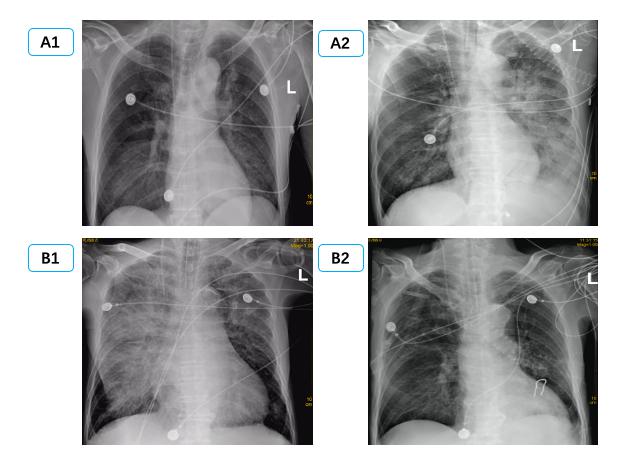

1.3 病例分组根据影像学表现分为双侧PE组和单侧PE组。单侧PE包括右侧和左侧PE(图 1图 2)。

| (C1、C2为同一患者,右侧PE,男,56岁,冠状动脉搭桥术后,C1为咳嗽咳痰1周入院时,C2为抗感染治疗14 d后。D1、D2为同一患者,左侧PE,女,32岁,眼眶下局麻后心脏骤停,D1为心脏骤停后3 h,D2为心脏骤停后24 h。) 图 2 单侧肺水肿CT表现 Fig 2 Manifestations of unilateral PE on CT |

2 结果通过病历系统回顾性分析2018年1月至2021年1月,共纳入314例患者,其中男性179例,女性135例,年龄18~97岁[(58.8±16.9)岁]。单侧PE患者共14例,发病率4.5%,男性10例,女性4例; 其中以右侧为主单侧PE 11例(78.5%),左侧PE患者3例(21.5%)。1例单侧PE呈右肺上叶局限性分布,(见图患者C),1例单侧PE以左下肺为主(见图患者A),其余单侧PE分布无明显肺段特点。

在本次试验中单侧PE发生率为4.5%,高于国外心内科单侧PE 2.1%发病率[2]。同时本次14例单侧PE中,主要(11例,78.5%)为右侧PE,与国外研究类似(16例,89%)[2]。本研究中,两组间左心室射血分数、左心房前后径、左心室舒张末内径等心脏超声参数均差异无统计学意义,与既往研究类似。同时该研究发现单侧PE患者重度二尖瓣反流比例高达100%[2]; 提示二尖瓣反流是导致单侧PE的主要原因。本研究中重度二尖瓣反流在单侧PE组发生率显著高于双侧PE组,35.7% vs 14.0%,但显著低于前述研究,可能与患者纳入标准有关,有5例(35.7%)因心室颤动等原因导致心脏骤停。其中如图 2中D患者,女,32岁,眼眶下局麻后心脏骤停。心脏骤停后3 hCT提示左肺弥漫渗出,但复苏8 h后查心脏超声无明显二尖瓣反流,考虑与心脏骤停冠脉缺血导致暂时性二尖瓣反流有关[25-26],因此24 h后复查CT左肺单侧PE完全消失。

除考虑二尖瓣偏心反流导致单侧或单支肺静脉压力升高,回流受阻,还可能与双侧肺静脉回流角度、大小有关。研究显示左心房入口处,右侧肺静脉相比左侧肺静脉其内径、横截面积均更大[27],同时右肺静脉与二尖瓣反流的角度更小,因此在二尖瓣导致的单侧PE以右侧为主[2],尤其是右上叶为主[9, 11],部分患者PE表现非常局限,常常误诊为肺部感染[9, 28],如图 2中C患者。但本研究中心脏骤停患者,心肺复苏按压时双侧肺静脉回流阻力是否有影响目前尚不明确。